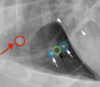

Is sternal lymphadenopathy present in this patient?

Yes.

Note the enlargement of the sternal lymph node

Is the circled lesion more likely in the lung or the mediastinum?

Lung

Note the acute angle to the body wall. If the lesion was in the lung you would not have such an acute angle